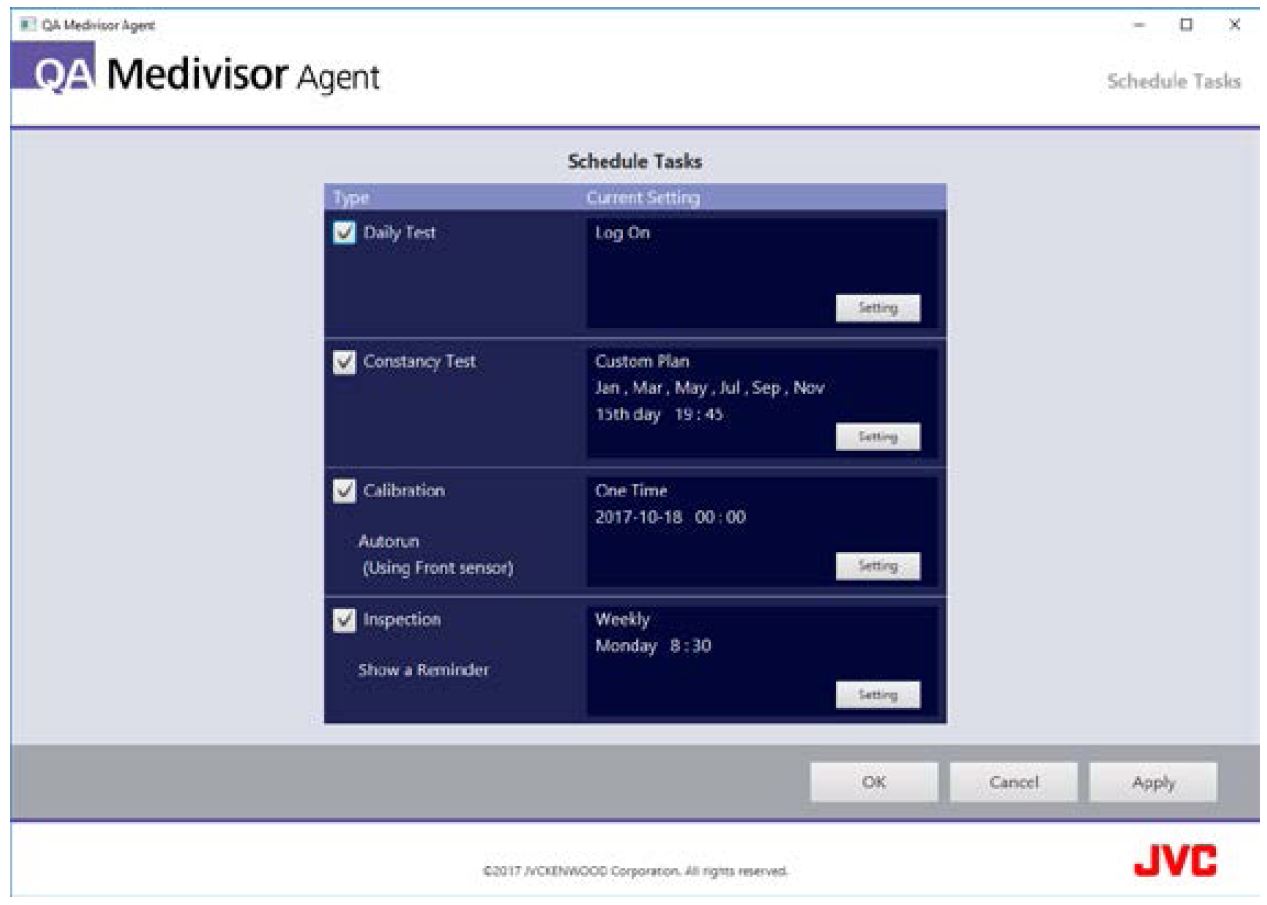

QA - Zintegrowany system kontroli jakości

Oprogramowanie QA Medivisor Agent zapewnia możliwość kalibracji i wykonania standardowych testów kontroli jakości QA*. Łatwy i intuicyjny w obsłudze interfejs ułatwia skuteczne i szybkie zarządzanie codzienną pracą w dziale radiologii.

Samodzielna kalibracja

Zintegrowany czujnik przedni w monitorach serii i3 pozwala na samodzielne, zgodnie z ustawionym harmonogramem, wykonanie przez monitor okresowej kalibracji do standardu DICOM.